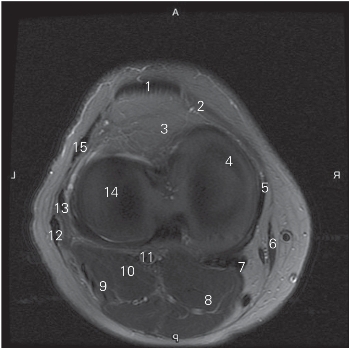

图5-23 经股骨内外髁的横断层MR T2WI FS

1 髌腱 patellar tendon 2 内侧支持带 medial retinaculum

3 髌下脂肪垫 infrapatellar fat pad

4 股骨内侧髁 medial condyle of femur

5 胫侧副韧带 tibial collateral ligament 6 缝匠肌 sartorius

7 半膜肌腱 semimembranosus tendon

8 腓肠肌内侧头 medial head of gastrocnemius

9 跖肌 plantaris

10 腓肠肌外侧头 lateral head of gastrocnemius

11 腘动、静脉 popliteal artery and vein

12 股二头肌肌腱 tendon of biceps femoris tendon

13 腓侧副韧带 fibular collateral ligament

14 股骨外侧髁 lateral condyle of femur 15 髂胫束 iliotibial tract